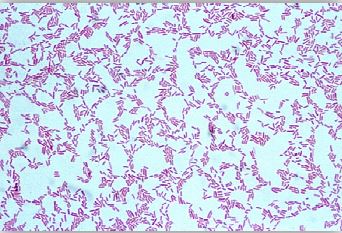

خلايا هذا الجنس البكتيري عبارة عن عصويات هوائية بحجم 0.6 عرض و 2 ميكرومتر طول، وهي سالبة لصبغة جرام غير مكونة للأبواغ . وهو متحرك بواسطة أسواط (سوط أو اثنين) تتواجد في قطبي الخلية كما أن بعض سلالات النوع البكتيري Pseudomnas aeruginosa قد يكون حافظة ويعتبر من أهم الأجناس البكتيرية الممرضة وذلك من أصل 200 نوع من هذا الجنس وله القدرة على النمو في درجة حرارة 42-37 درجة مئوية ويفرز صبغتين قابلتين للذوبان وهما صبغة pyocyanin الذي يكسبها اللون الأزرق عند تنميته في المعمل وصبغة Pyoverdin الذي يكسبه اللون الأصفر المخضر وهذه الصبغة تفرز بكثرة في الوسط الغذائي الذي يحتوي على مقدار قليل من الحديد وهناك نوعان آخران من الصبغات يفرزهم هذا الجنس البكتيري وهما صبغة pyorubrin الذي يكسبها اللون الأحمر وصبغة Melanin الذي يكسبها اللون البني ومن المعروف قدرة هذه البكتيريا على مقاومة المضادات الحيوية.

خلايا النوع البكتيري P. aeruginosaبصبغة جرام